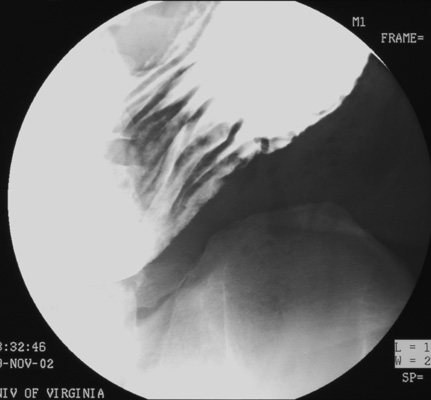

- Then, use compression cone on fluoroscope and take four SCGC spots (Zoom to 6" or 9" FOV) of:

- Gastric antrum (patient LPO)

- Gastric antrum/body (patient LPO or AP)

- Gastric body (patient AP)

- Gastric body/fundus (patient RPO)